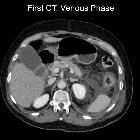

Necrotizing

pancreatitis: peripancreatic necrosis alone. Acute necrotic collections (ANCs), affecting retroperitoneal spaces: left anterior pararenal space, with upper extension to subphrenic space.